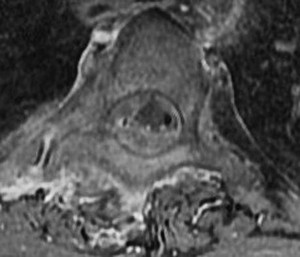

Question 80

A 55-year-old Asian male presents with progressive clumsiness in his hands and a wide-based gait. Imaging reveals ossification of the posterior longitudinal ligament (OPLL) from C3 to C6. The sagittal MRI shows that the OPLL mass crosses the K-line (K-line negative), and the cervical spine has 15 degrees of local kyphosis. Which surgical approach is most appropriate?

Explanation